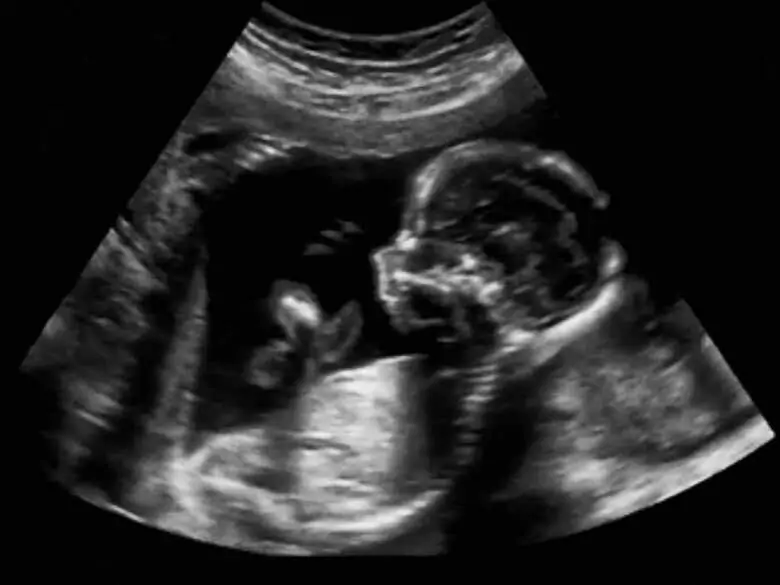

Foto ojoimages